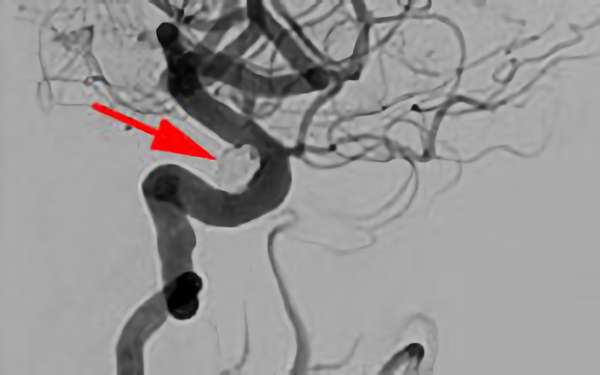

'26年4月

左後下小脳動脈瘤

80代

大阪府の病院

No.1631 手術前

No.1631 手術中

No.1631 手術後